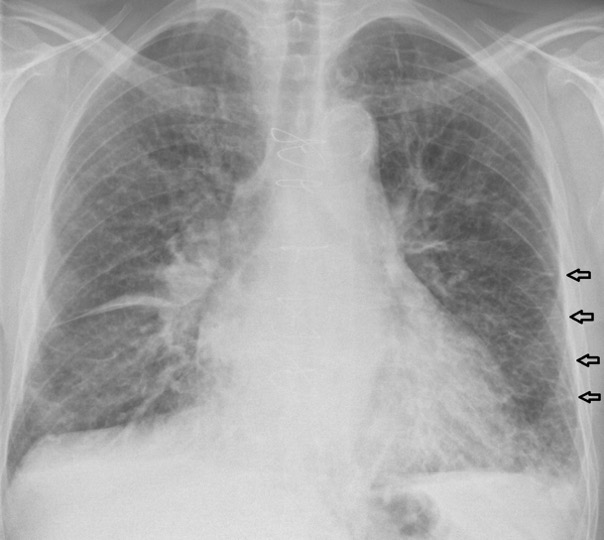

- Pulmonary oedema….?

- HD patients develop pulmonary oedema for a number of reasons:

- Too much fluid in (drinking too much or overzealous IV fluid) or not enough fluid out(missed HD sessions, under-dialysis)

- Heart failure (e.g. due to MIs, diastolic dysfunction from hypertension/LVH)